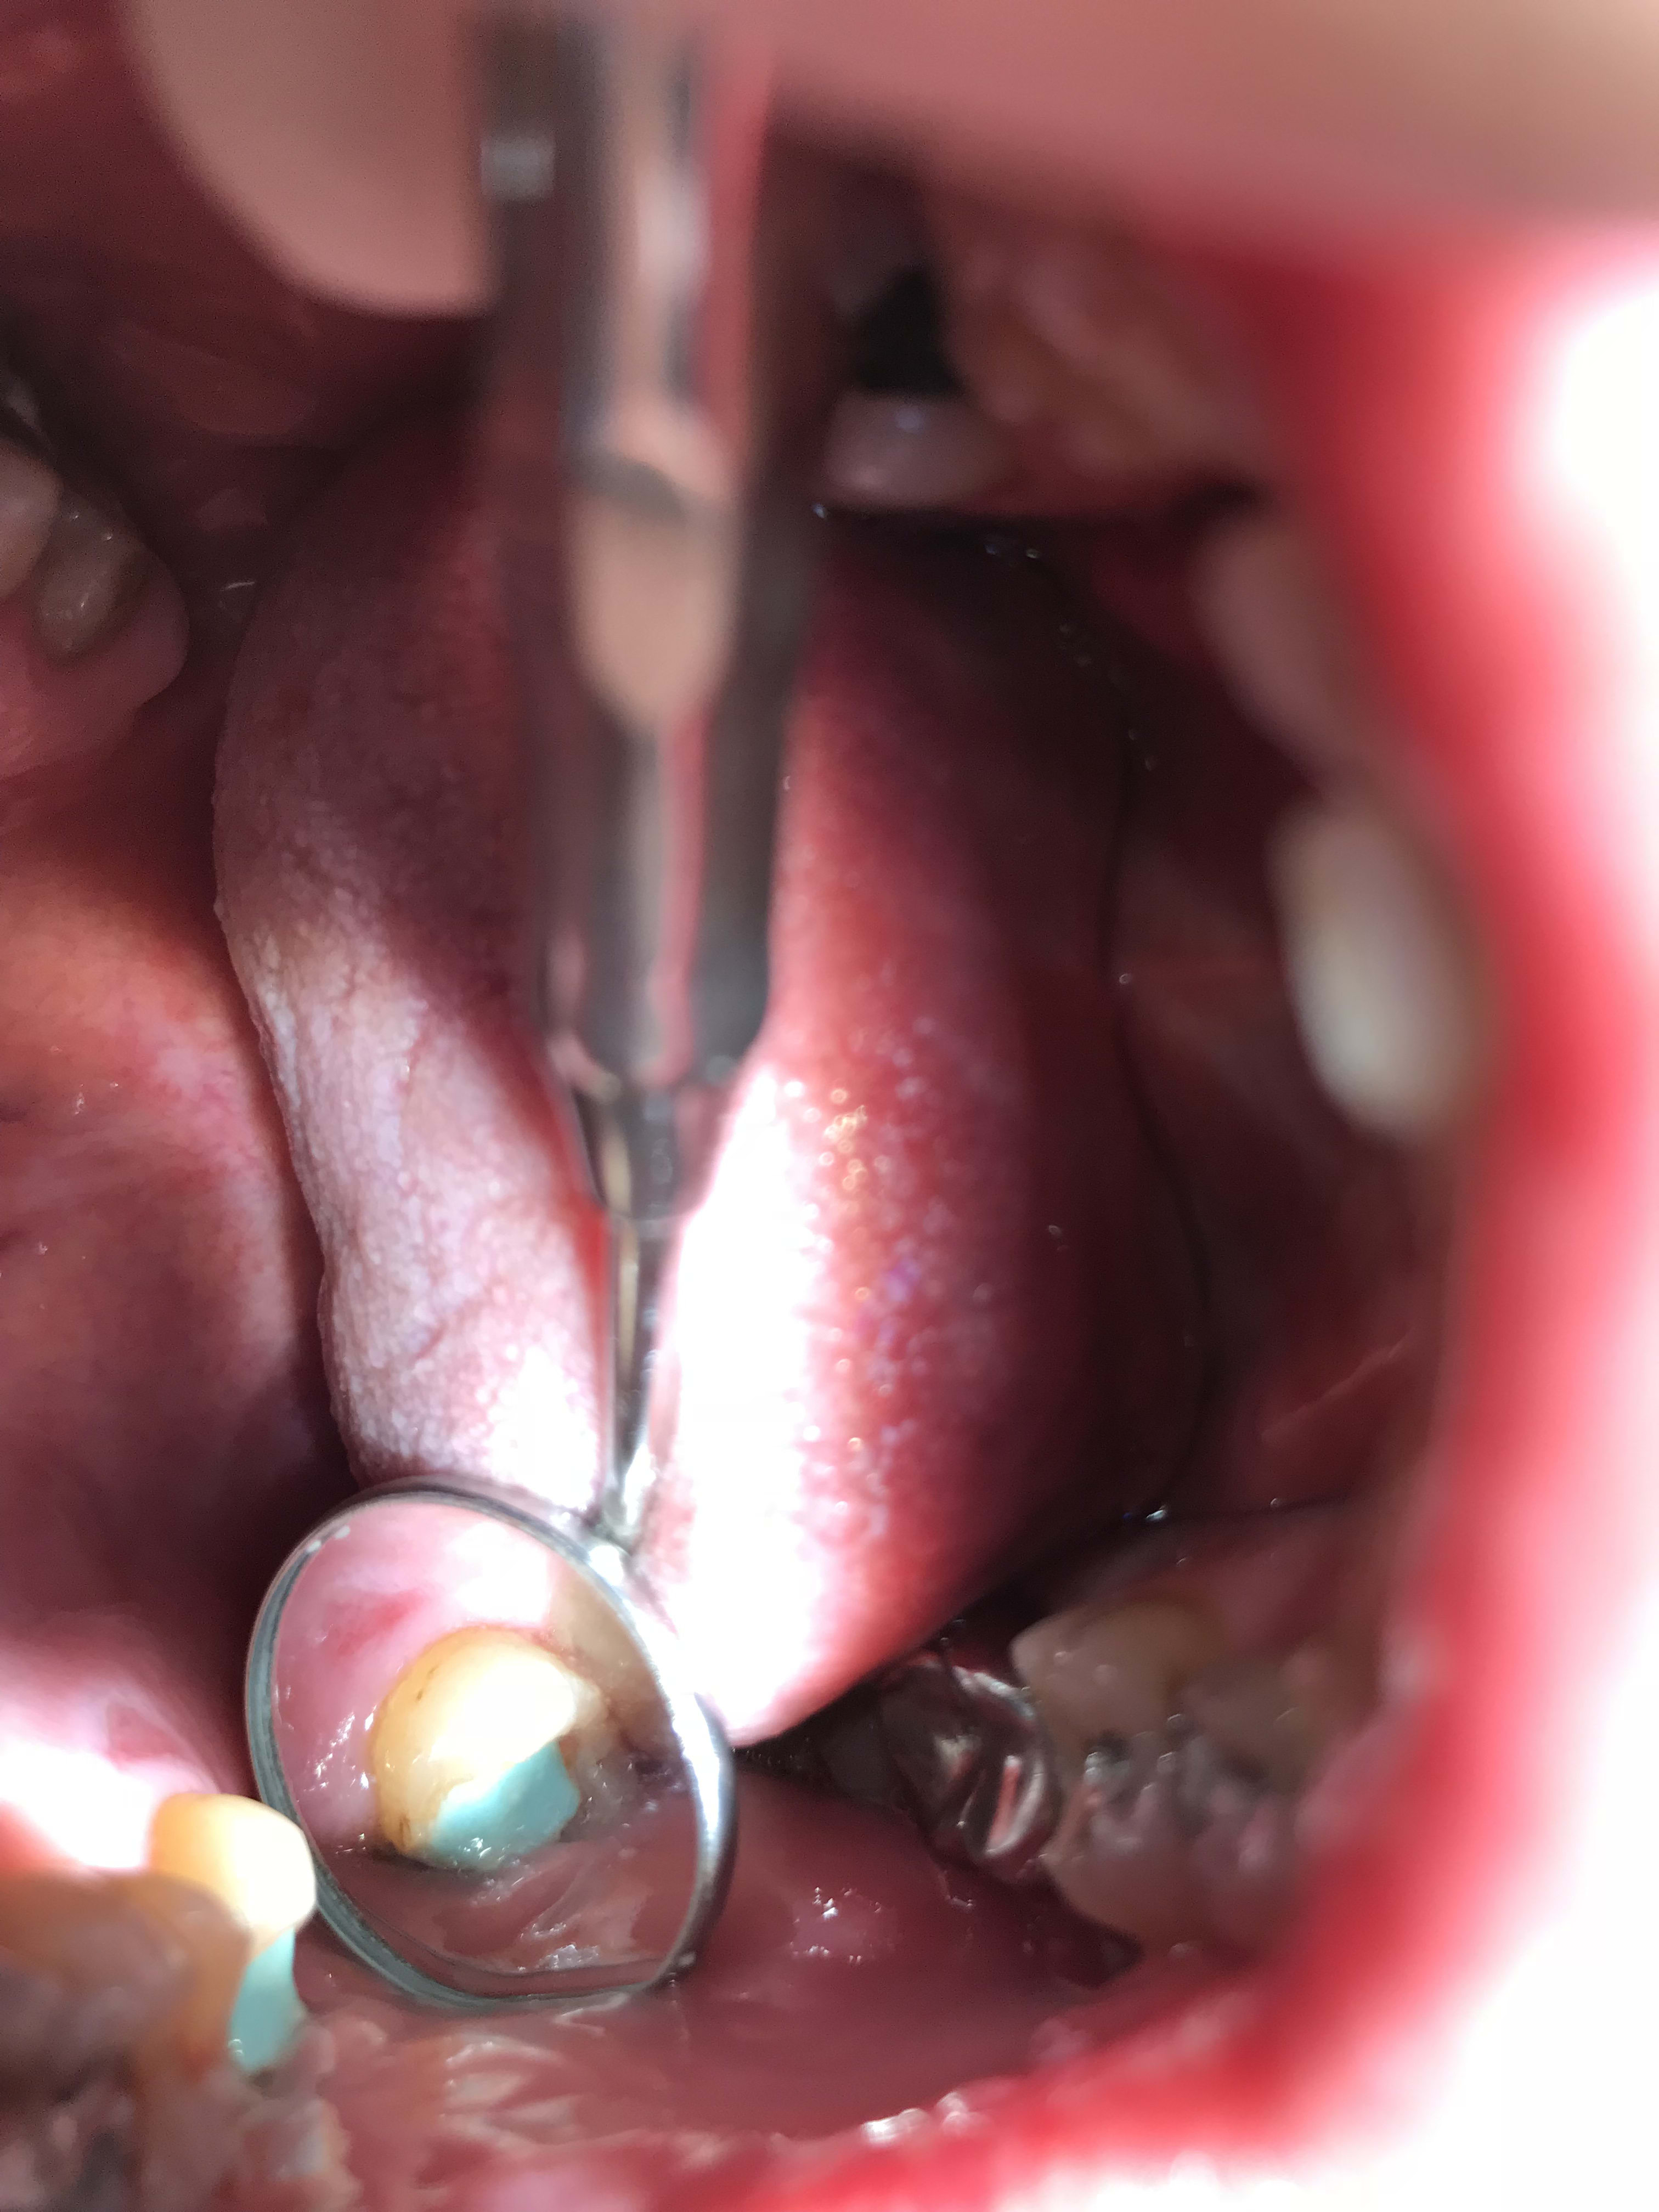

Y en a un qui peut m’expliquer ce qu’est ce trafic ? J’ai trouvé un truc en or sous une couronne

Moi je ne comprends pas . Pourquoi mettre un IC or sous une CCM

- 12 à extraire

- extraction

- 13 je retire la CCM

- oh putinnn surprise du chef : de l’or dessous ! C’est quoi ce délire encore ! Ces vieilles branches m’auront tout fait !

- bridge provisoire

Avec 1IC en or l etancheité etait top , et aucun risque de fracture radiculaire .

Par dessus tu mettais une ccm chappe or blanc ou civ or jaune

sinon pour moi c'est une ex Richmond or/résine qui à été retaillé dans la masse pour faire un moignon pour une CCM.

Tu démonte la CCM et tu te retrouve avec un truc bizarre mi or mi oxyphosphate.

T’as peut être raison car quand j’ai retouché au moignon , on voit des zones où y a du ciment

Ça ressemble plutôt à une vieille richmond en or qui a été retaillée pour éviter la galère de la dépose.

Qu’ est ce que c’est que ce trafic ? Ah ben bravo la compagnie ! C’est du propre ! Du composite vert on aura tout vu :))) c’etait la période psychédélique de la dentisterie ? C’est après avoir fumé combien de moquettes que vous avez eu l’idee de mettre des compos verts ? ^^

Normalement il est bleu .il a du verdir alors .c est un compo pour moignons .